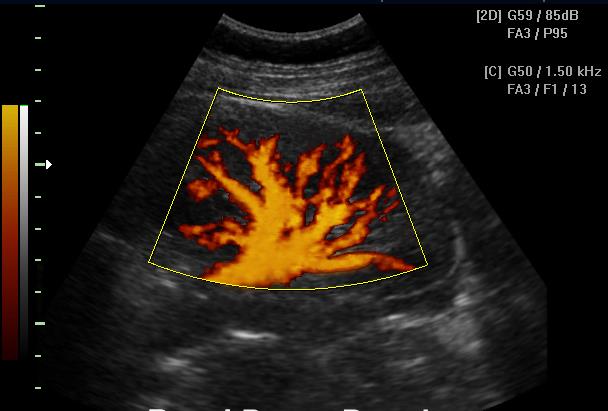

PDI (CDE, CPA, PDF, PD, PF, ЭДК и т.д.) – режим ЦДК «энергии» допплеровского спектра

Режим «энергетического» допплера является модификацией режима ЦДК и отличается от него тем, что режим ЭДК отражает движение в исследуемой области и его интенсивность, но информация о скорости и направлении при этом отсутствует. Режим ЭДК обладает практически полной независимостью от величины допплеровского угла.

Основное преимущество данного метода состоит в том, что режим ЭДК позволяет кодировать низкоскоростные потоки с значительно более высоким качеством, нежели в режиме ЦДК. Основной недостаток – большая чувствительность к любому движению, как датчика, так и исследуемой структуры.

1.jpg